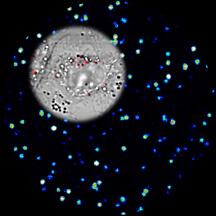

New research findings suggest that an experimental ultrasensitive imaging technique that uses a pulsed laser and tiny metallic "nanocages" might enable both the early detection and treatment of disease. This composite image shows luminous nanocages, which appear like stars against a black background, and a living cell, at upper left. The gold-silver nanocages exhibit a bright "three-photon luminescence" when excited by the ultrafast pulsed laser, with 10-times greater intensity than pure gold or silver nanoparticles. The signal allows live cell imaging with negligible damage from heating. (Purdue University graphic/Ji-Xin Cheng)

The gold-silver structures yielded images 10 times brighter than other experimental imaging research using gold nanospheres and nanorods. The imaging technology provides brightness and contrast potentially hundreds of times better than conventional fluorescent dyes used for a wide range of biological imaging to study the inner workings of cells and molecules.

The new imaging approach uses a phenomenon called "three-photon luminescence," which provides higher contrast and brighter images than conventional fluorescence imaging methods. Normally, three-photon luminescence is too dim to be used for imaging. However, the presence of gold and silver nanoparticles enhances the brightness, overcoming this obstacle. The ultrafast laser also is thought to possibly play a role by causing "third harmonic generation," which increases the brightness.